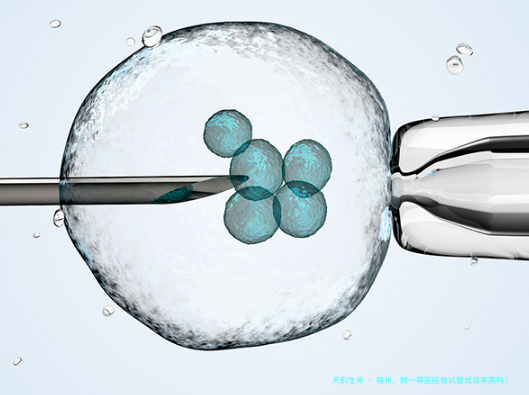

福州附顶尖医院,就是福建医科大学所属一级医院,是一家具有较高声誉和作用力的医疗组织,在辅助生殖医学领域也有着一定的研究基础和技术能力。关于试管婴儿技术的成功率,通常会受到许多种因素的影响,包括但不仅限于女的一方岁数、男方精液质量、胚胎质量、子宫腔内环境以及医疗团体的专业水同等。

该医院的生殖医院拥有一支由资深专家造成的集体,他们在辅助生育技术标的目的累积了丰富的经验。集体成员不光具备踏实的理论学问,还经常参加国表里学术交流活动,及时把握最新的研究成果和技术进展。此外医院还引进了国际卓越的辅助生育技术,如单精子注射(显微受精技术)、胚胎保存等,以提高试管婴儿的成功率。

福建医学学科大学所属一级医院在试管婴儿技术方面有着较高的成功率,这必须益于其强盛的技术力量和优良的医疗服务。然而每一个病患的具体情况不同,最终的成功率亦会有所差别。如若您思考在这儿做试管婴儿手术,建议提前咨询专业医生,详细认识自我状况,并根据医生的建议做出合理选择。